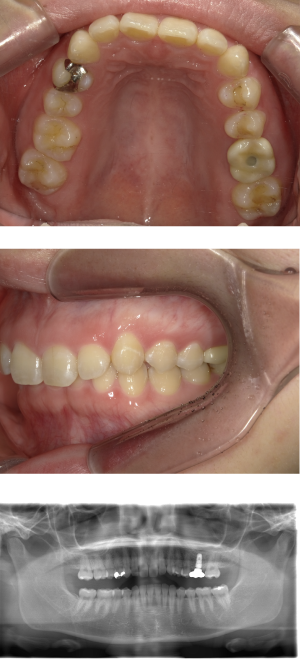

30代 女性 インプラント治療(GBR・ソケットリフト)

| 年代・性別 | 30代・女性 |

|---|---|

| 主訴 | 縁下まで虫歯が進行し、抜歯へ。カウンセリングし、インプラント希望。 |

| 部位 | 右上7 |

| 治療期間 | 約7ヶ月 |

| 費用 | ¥500,500(税込) |

| 副作用・リスク |

|